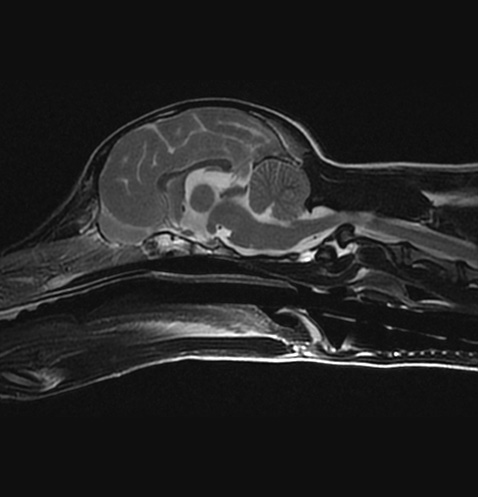

자기공명영상(MRI) 검사

MRI는 자기장 내에서 신체에 고주파를 전사해 반향되는 전자기파를 측정 및 재구성하여 영상을 얻어 질병을 진단하는 검사로, 일반 방사선 검사(x-ray), 전단화 단층 촬영(CT)과 비교하여 방사선 피폭이 없고, 영상 대조도 및 해상도가 연부 조직과 뇌 검사에 뛰어난 장점을 가집니다. MRI는 뇌수두증이나 뇌종양 등 두개내 질환, 디스크탈출, 척수 질환 및 관절염과 인대 파열 등의 관절 질환의 평가에 유용하며 병변의 정확한 진단에 도움을 주고, 이를 통해 이후 빠른 내∙외과적인 치료를 가능하게 합니다.